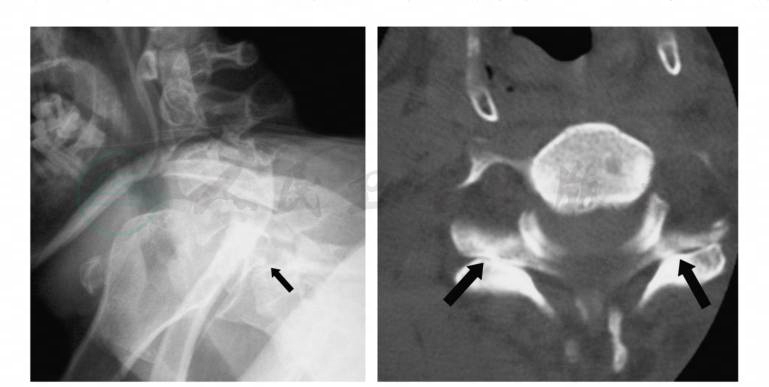

图1X线及CT显示C5~6双侧小关节脱位

X线侧位片上损伤节段椎体前移的距离至少是椎体前后径的1/2,上位椎体的下关节突位于下位椎体上关节突的顶部或前方,棘突间的距离加大。正位片上钩椎关节关系紊乱,小关节相互关系显示不清。CT可显示典型的双侧小关节脱位征,CT和MRI还有助于鉴别双侧还是单侧脱位。